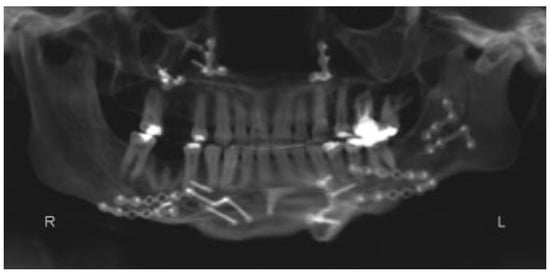

:Case Report